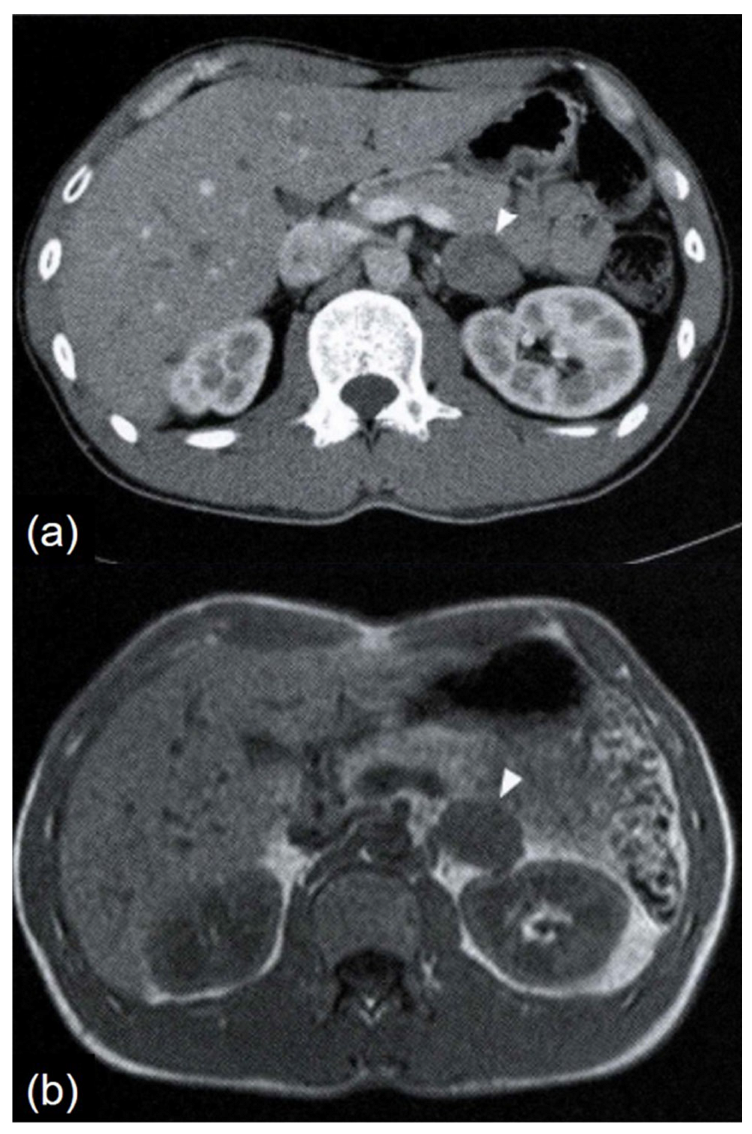

Abdominal computed tomography (CT) and magnetic resonance imaging (MRI) revealed a well-defined, smoothly bordered left adrenal tumor measuring 3.3 × 2.3 cm. The tumor appeared as a soft tissue density on plain CT, with no evidence of calcification. On contrast-enhanced CT, it showed slight heterogeneous enhancement (Figure 1a). On T1-weighted MRI images, the tumor appeared iso-intense to skeletal muscle (Figure 1b). It was mildly hyperintense compared to skeletal muscle on T2-weighted images, with no signal loss on out-of-phase imaging. No findings suggested fat content. Contrast-enhanced MRI revealed uniform moderate enhancement. 123I-metaiodobenzylguanidine scintigraphy showed no abnormal accumulation. Laparoscopic left adrenalectomy was subsequently performed.

Figure 1. Radiological findings. (a) Abdominal contrast-enhanced CT: The tumor appears slightly heterogeneous, presenting as a contrast-enhancing hypodense solid mass (arrowhead). (b) Abdominal T1-weighted MRI image: The tumor shows isointensity with skeletal muscle (arrowhead).